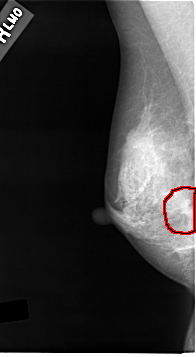

C_0015_1.RIGHT_MLO

RIGHT_MLO LINES 4632 PIXELS_PER_LINE 2544 BITS_PER_PIXEL 12 RESOLUTION 50 OVERLAY

FILE: C_0015_1.RIGHT_MLO.OVERLAY

TOTAL_ABNORMALITIES 1

ABNORMALITY 1

LESION_TYPE MASS SHAPE IRREGULAR MARGINS SPICULATED

ASSESSMENT 5

SUBTLETY 5

PATHOLOGY MALIGNANT

TOTAL_OUTLINES 1

BOUNDARY